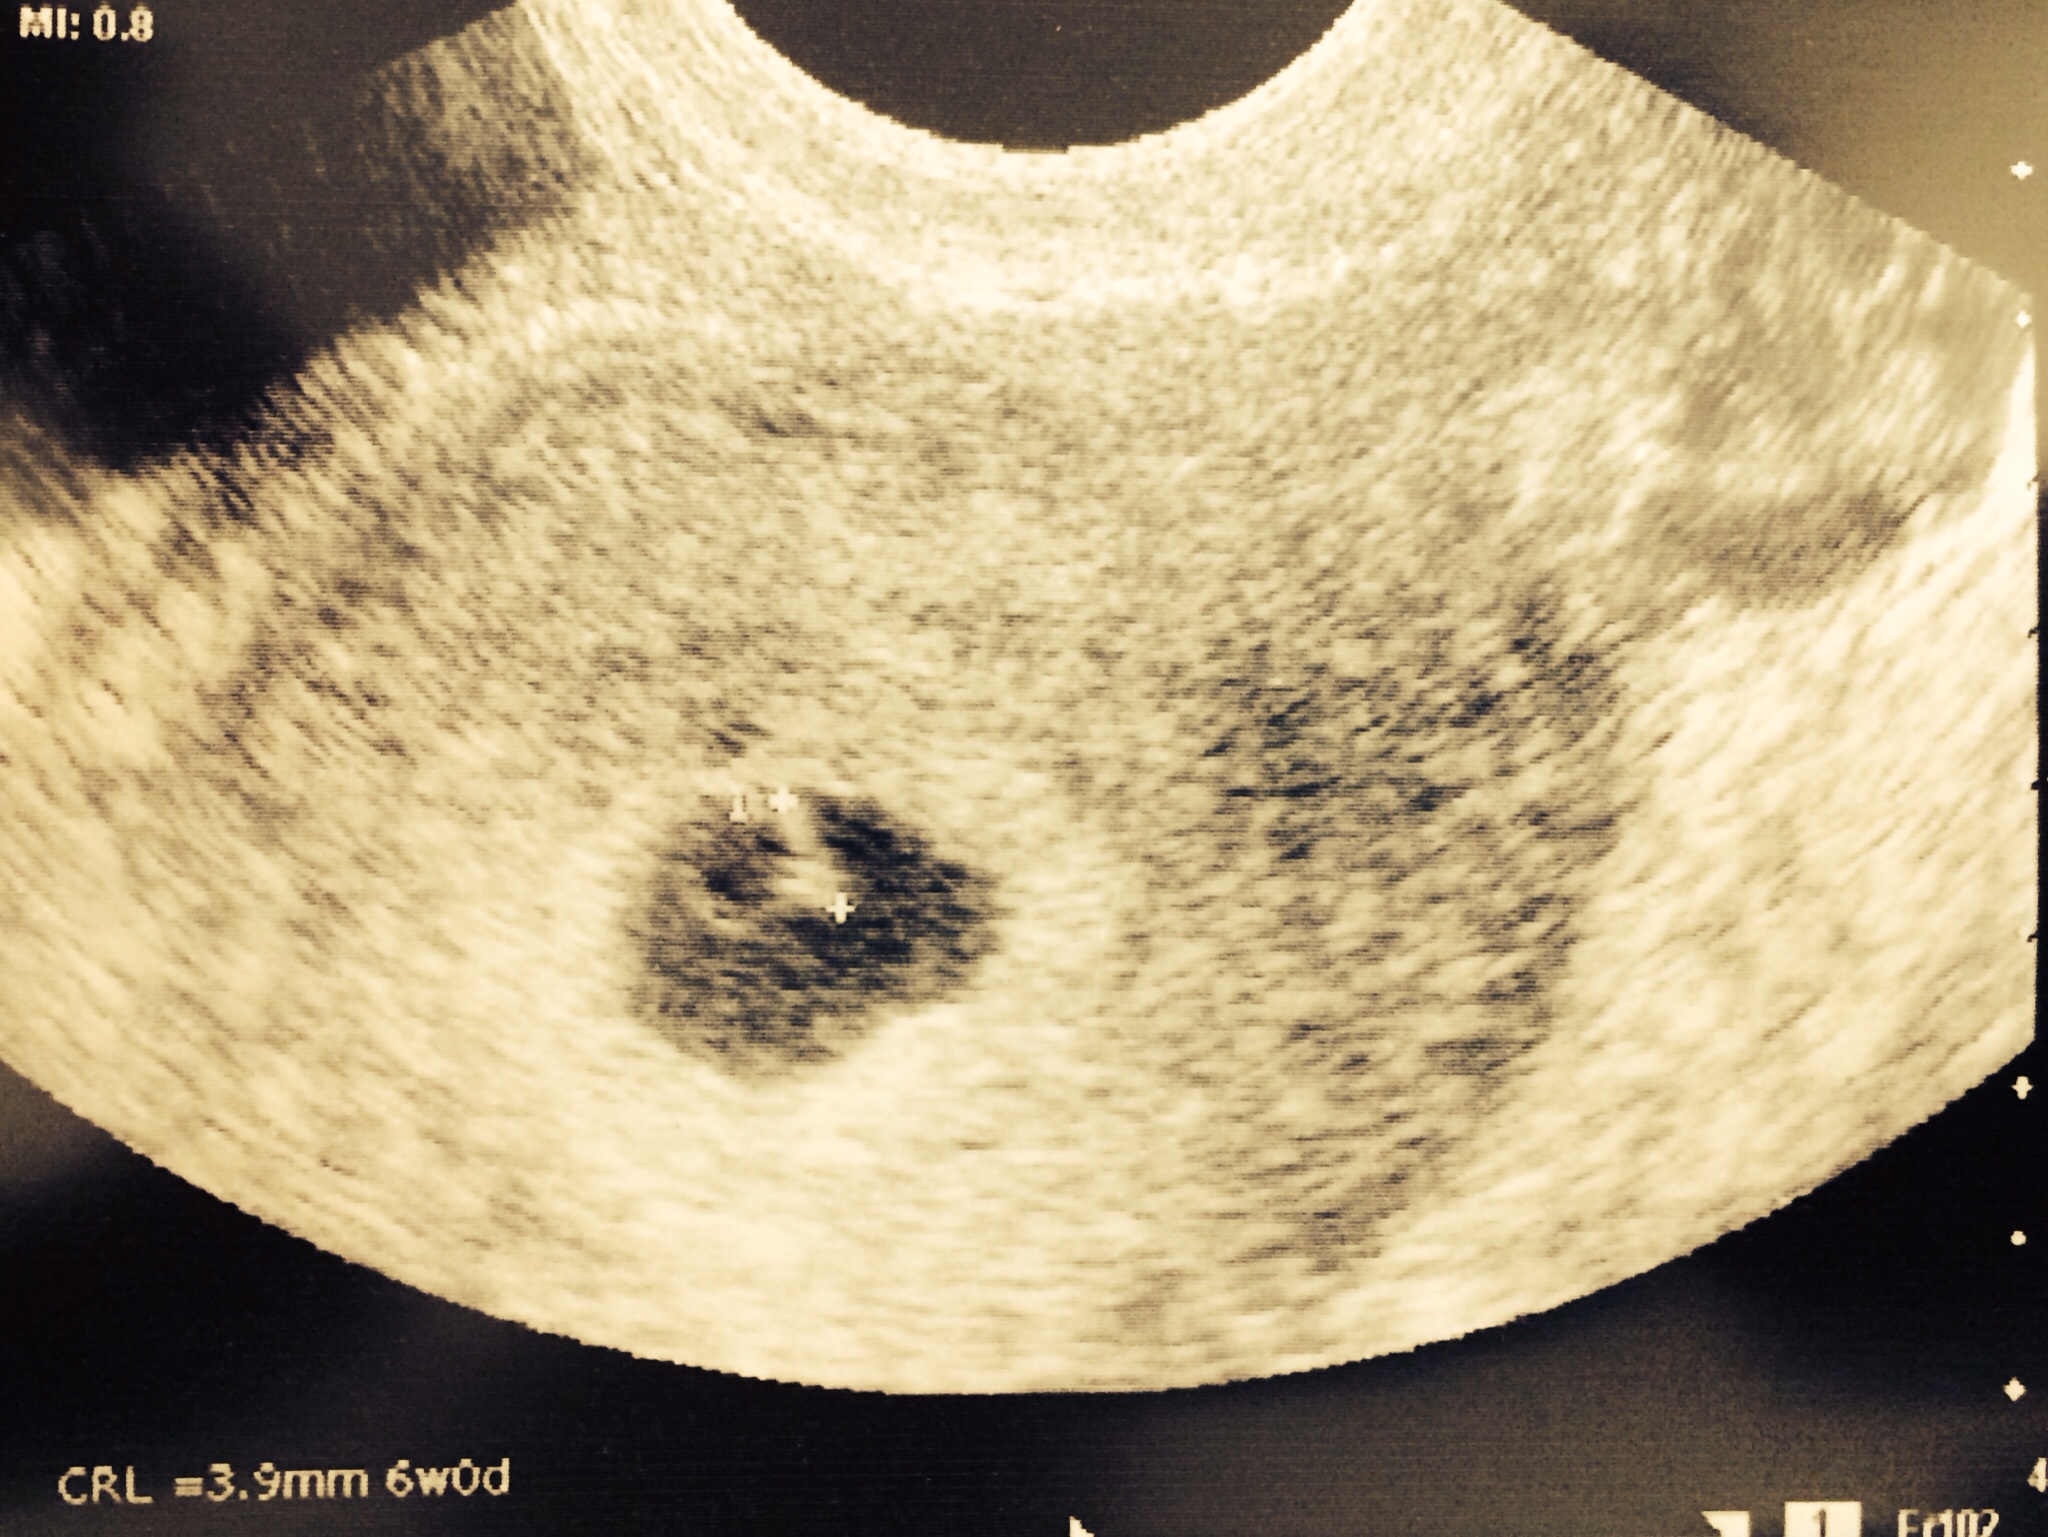

We had our first appointment on Monday and got our first glimps of our little jelly bean with a heart beat!!! So relieved!!!! Doctor confirmed due date of June 1st so I was only 6w0d on Monday and he said that he was a little surprised to see the heart beat just because it was still pretty early.

He said that there is a less that 5% chance of anything going wrong now! He said that the next important development phase is between week 7-8 when all the organs develop. I have a follow-up appointment on the 23rd (at 8 1/2 weeks) so he said if everything looks good then then there would be less than a 2% chance of a loss! Yay!!!